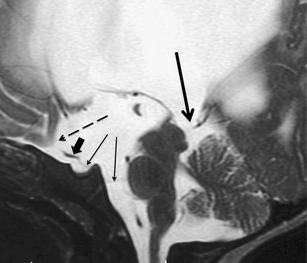

The sylvian aqueduct is the most common site of intraventricular blockage of the cerebro-spinal fluid. Clinical aspects, neuroradiological appearance, and treatment of hydrocephalus secondary to aqueductal stenosis are specific.

The correct interpretation of the modern neuroradiologic techniques may help in selecting adequate treatment between the two main options (third ventriculostomy or shunting). In the last decades, endoscopic third ventriculostomy has become the first-line treatment of aqueductal stenosis; however, some issues, such as the cause of failures in well selected patients, long-term outcome in infant treated with ETV, and effect of persistent ventriculomegaly on neuropsychological developmental, remain unanswered.